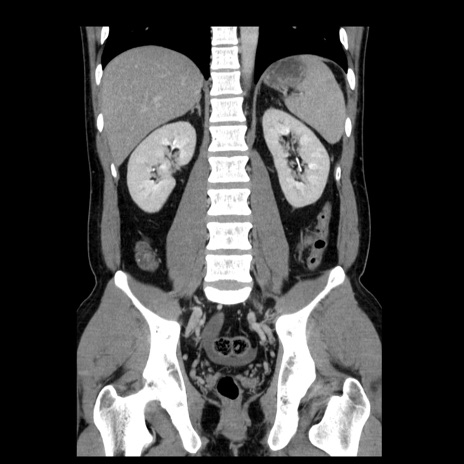

症例4(冠状断像)

【症例】30歳代男性

【主訴】腹痛、嘔吐

【現病歴】昨晩から突然の腹痛あり、その後嘔吐、軟便も出現。腹痛が改善しないため救急搬送となる。2日前にしめ鯖の食事歴あり。

【身体所見】意識清明、苦悶様、BP 135/90mmHg、BT 35.7℃、腹部:平坦、やや硬、心窩部〜臍部に自発痛、圧痛あり、筋性防御+、反跳痛-

【データ】WBC 8100、CRP 0.57